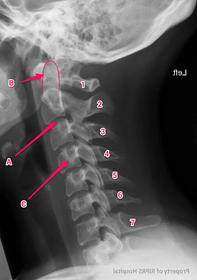

Anatomy practical midyear flashcard revision

anatomy

x-ray